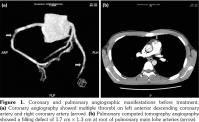

A 22-year-old male patient was admitted to our department in 2013. He had a history of recurrent erythema nodosum in lower limbs for over a two-year period. For the past one year, the patient complained of recurrent oral ulcer and arthralgia. For the past four months, he experienced low grade fever. In addition to fever, facial acneiform lesions were also noticed. Meanwhile, he also suffered chest pain which radiated to the left shoulder back. Physical examinations showed acne-like rashes over face and back, and erythema nodosum in limbs. Multiple minor ulcers were present on the buccal mucosa. Laboratory investigation revealed hemoglobin of 106 g/L, erythrocyte sedimentation rate of 120 mm/ hour, and C-reactive protein of 152 mg/L. Procalcitonin, myocardial enzymes, troponin I, antinuclear antibody and other autoantibodies were all negative. Bone marrow morphology showed poisoning changes. Electrocardiogram demonstrated lower ST segment on V2-V6 and T wave inversion on the V4-V6 lead. Then, the patient received coronary angiography that showed multiple coronary thrombi, and the stenosis reached about 90% (Figure 1a) at the root of the pulmonary artery. Pulmonary computed tomography angiography was also performed, which showed filling defects at the root of pulmonary main lobe arteries (Figure 1b). At the same time, positive pathergy test appeared on the site of bone marrow puncture. According to the International Criteria of BD(4) the patient was diagnosed as BD with oral ulcers, skin lesions, positive pathergy test and cardiovascular involvement. He was given immunosuppressive therapy, which covered oral prednisone 40 mg daily along with cyclophosphamide 500 mg every two weeks. After a two-month treatment, coronary angiography and pulmonary computed tomography angiography revealed that thrombi obviously shrunk (Figure 2). The dosage of prednisone and cyclophosphamide were tapered gradually. To date, the coronary and pulmonary artery thrombosis have regressed without recurrence for nearly four years. A written informed consent was obtained from the patient.